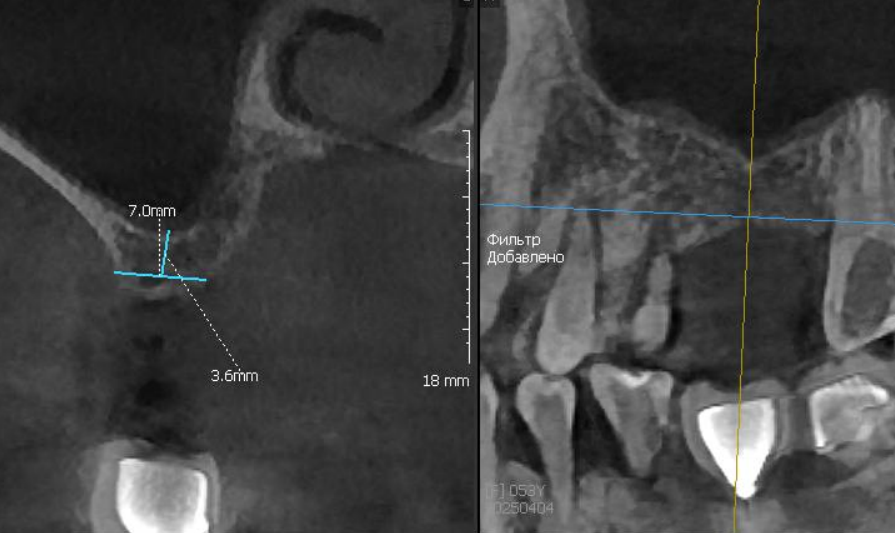

Закрытый синус-лифтинг, выполненный вогнутым остеотомом, с показательным срезом КТ после операции.

Виден смещенный фрагмент кости и Шнейдерова мембрана, которая была без повреждений поднята вслед за костью.